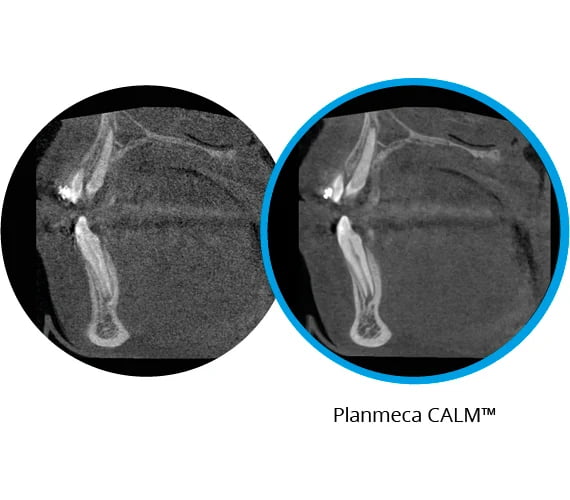

Korekcja nieostrych artefaktów

Ruch pacjenta jest poważnym problemem dla jakości obrazu, ale algorytm korekcji ruchu CALM® firmy Planmeca skutecznie eliminuje artefakty na obrazach CBCT spowodowane ruchem pacjenta, zapewniając zawsze dokładne obrazy.